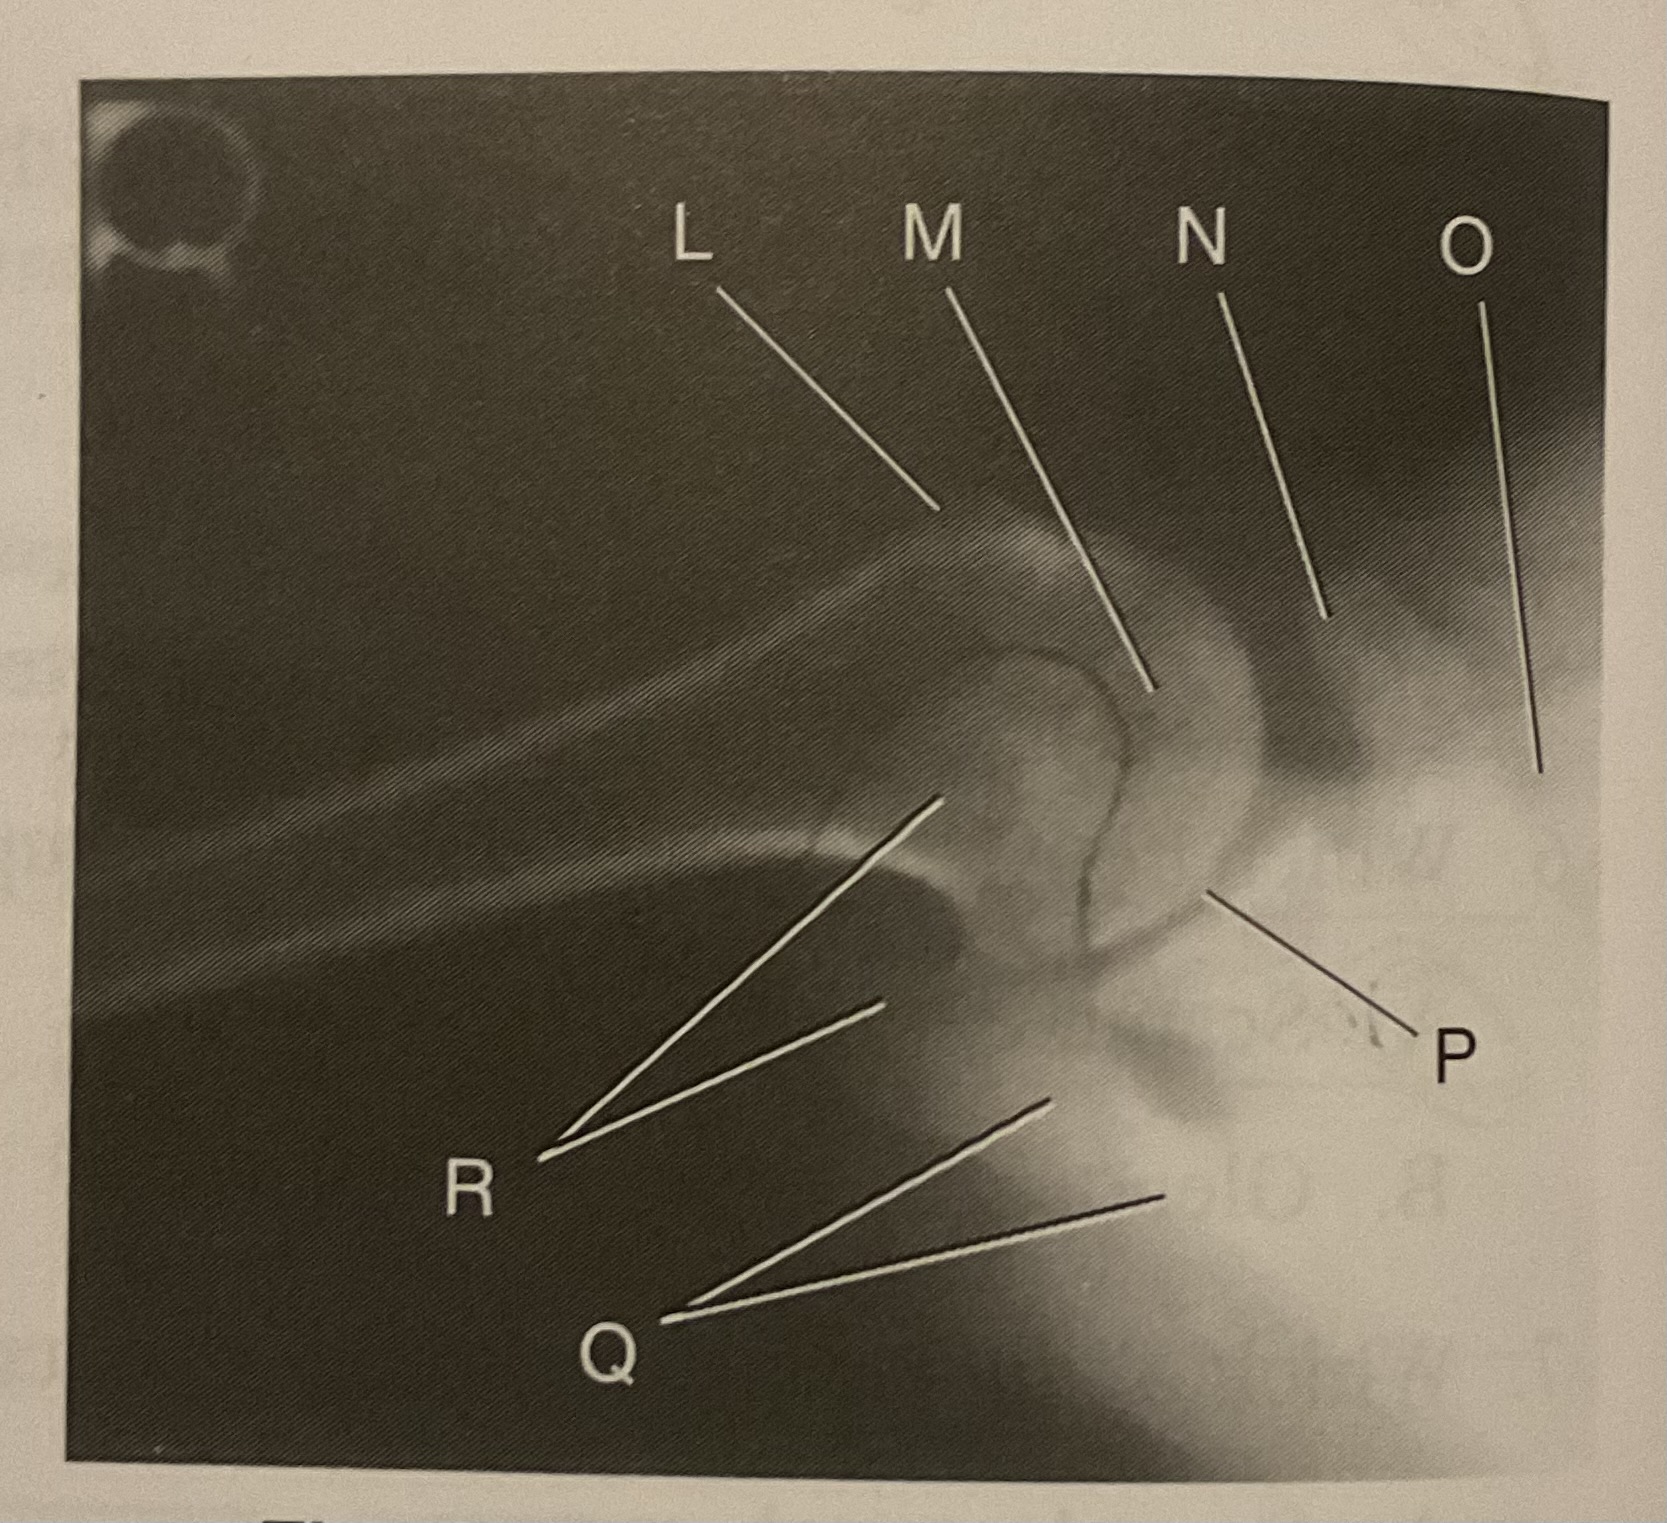

L?

Lesser tubercle

M?

Head of humerus

N?

Coracoid process

O?

Clavicle or lateral extremity of clavicle

P?

Glenoid cavity or Scapulohumeral joint

Q?

Spine of scapula

R?

Acromion of scapula

What is the correct term and method for the projection seen in this image?

Inferosuperior axial projection